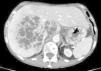

A second CT scan showed ascites, coarse calcifications in the head of the pancreas with retrograde dilatation of the pancreatic duct, and 2 pseudocysts in the body measuring 12mm×11mm and 22mm×16mm, which were connected by a tubular formation with a large bilobar hepatic lesion that was cystic and multiseptated, measuring 13cm×10cm. Hypertrophy of the posterior hepatic segments was also detected (Figs. 1 and 2).

In the context of chronic pancreatitis with pancreatic ascites, pancreatic pseudocysts are considered the probable origin of hepatic lesions, although a priori other causes cannot be ruled out, such as metastasis. Therefore, ultrasound-guided diagnostic fine-needle aspiration was used. The amylase levels in the fluid was 49180IU/L, and the pathology study was negative for malignancy, with normal hepatocytes.